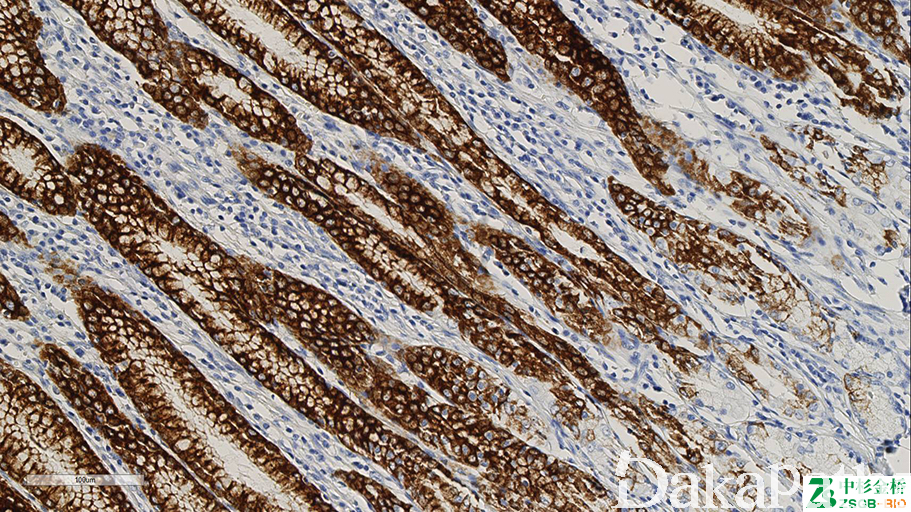

MUC5AC

正常只表达于胃型上皮(包括壶腹),又称胃型黏液。MUC 系列用于黏液性肿瘤黏液上皮分化类型的鉴别。

信号定位: 胞质